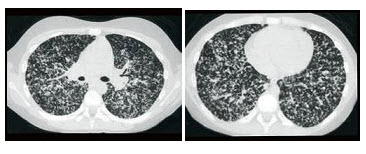

94、单项选择题

女,19岁,低热,盗汗,乏力,咳嗽1月余,CT检查如图,最可能的诊断是()

A.间质性肺炎

B.弥漫型肺癌

C.粟粒型肺结核

D.矽肺

E.大叶性肺炎